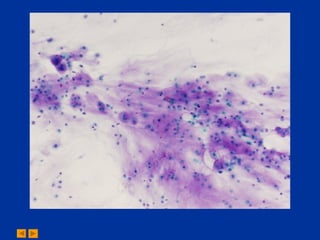

A 36-year-old female presented with a left popliteal mass. The differential diagnosis for the fine needle aspiration of the mass included chondroma and chondrosarcoma. The diagnosis from the cytopathology conference was chondrosarcoma.